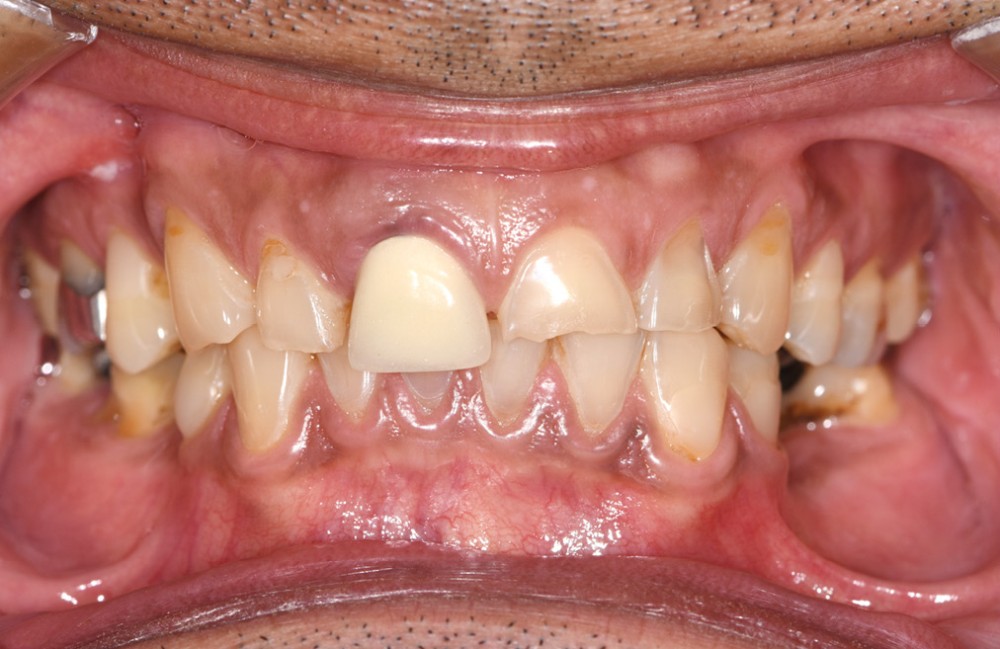

L’usure dentaire est de plus en plus fréquente au sein de nos cabinets. Nos patients y sont sujets de par leur alimentation parfois plus acide, leur mode de vie souvent plus stressant, et également une hygiène qui s’améliore et des dents qui vieillissent davantage.

L’étiologie de cette usure est multifactorielle, revêtant une composante de type attrition (usure par contact dento-

dentaire), une composante abrasive avec un brossage traumatique et, en dernier lieu, une légère composante tribo-érosive de par une pratique importante de sport avec gel et boisson acide (fig. 1-4) [1].